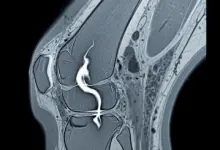

Os exames de imagem ajudam a confirmar a suspeita e a definir a extensão da ruptura. Os mais usados são:

- Ressonância magnética.

A ressonância tem um papel importante quando existe dúvida clínica ou necessidade de avaliar melhor o padrão da lesão.